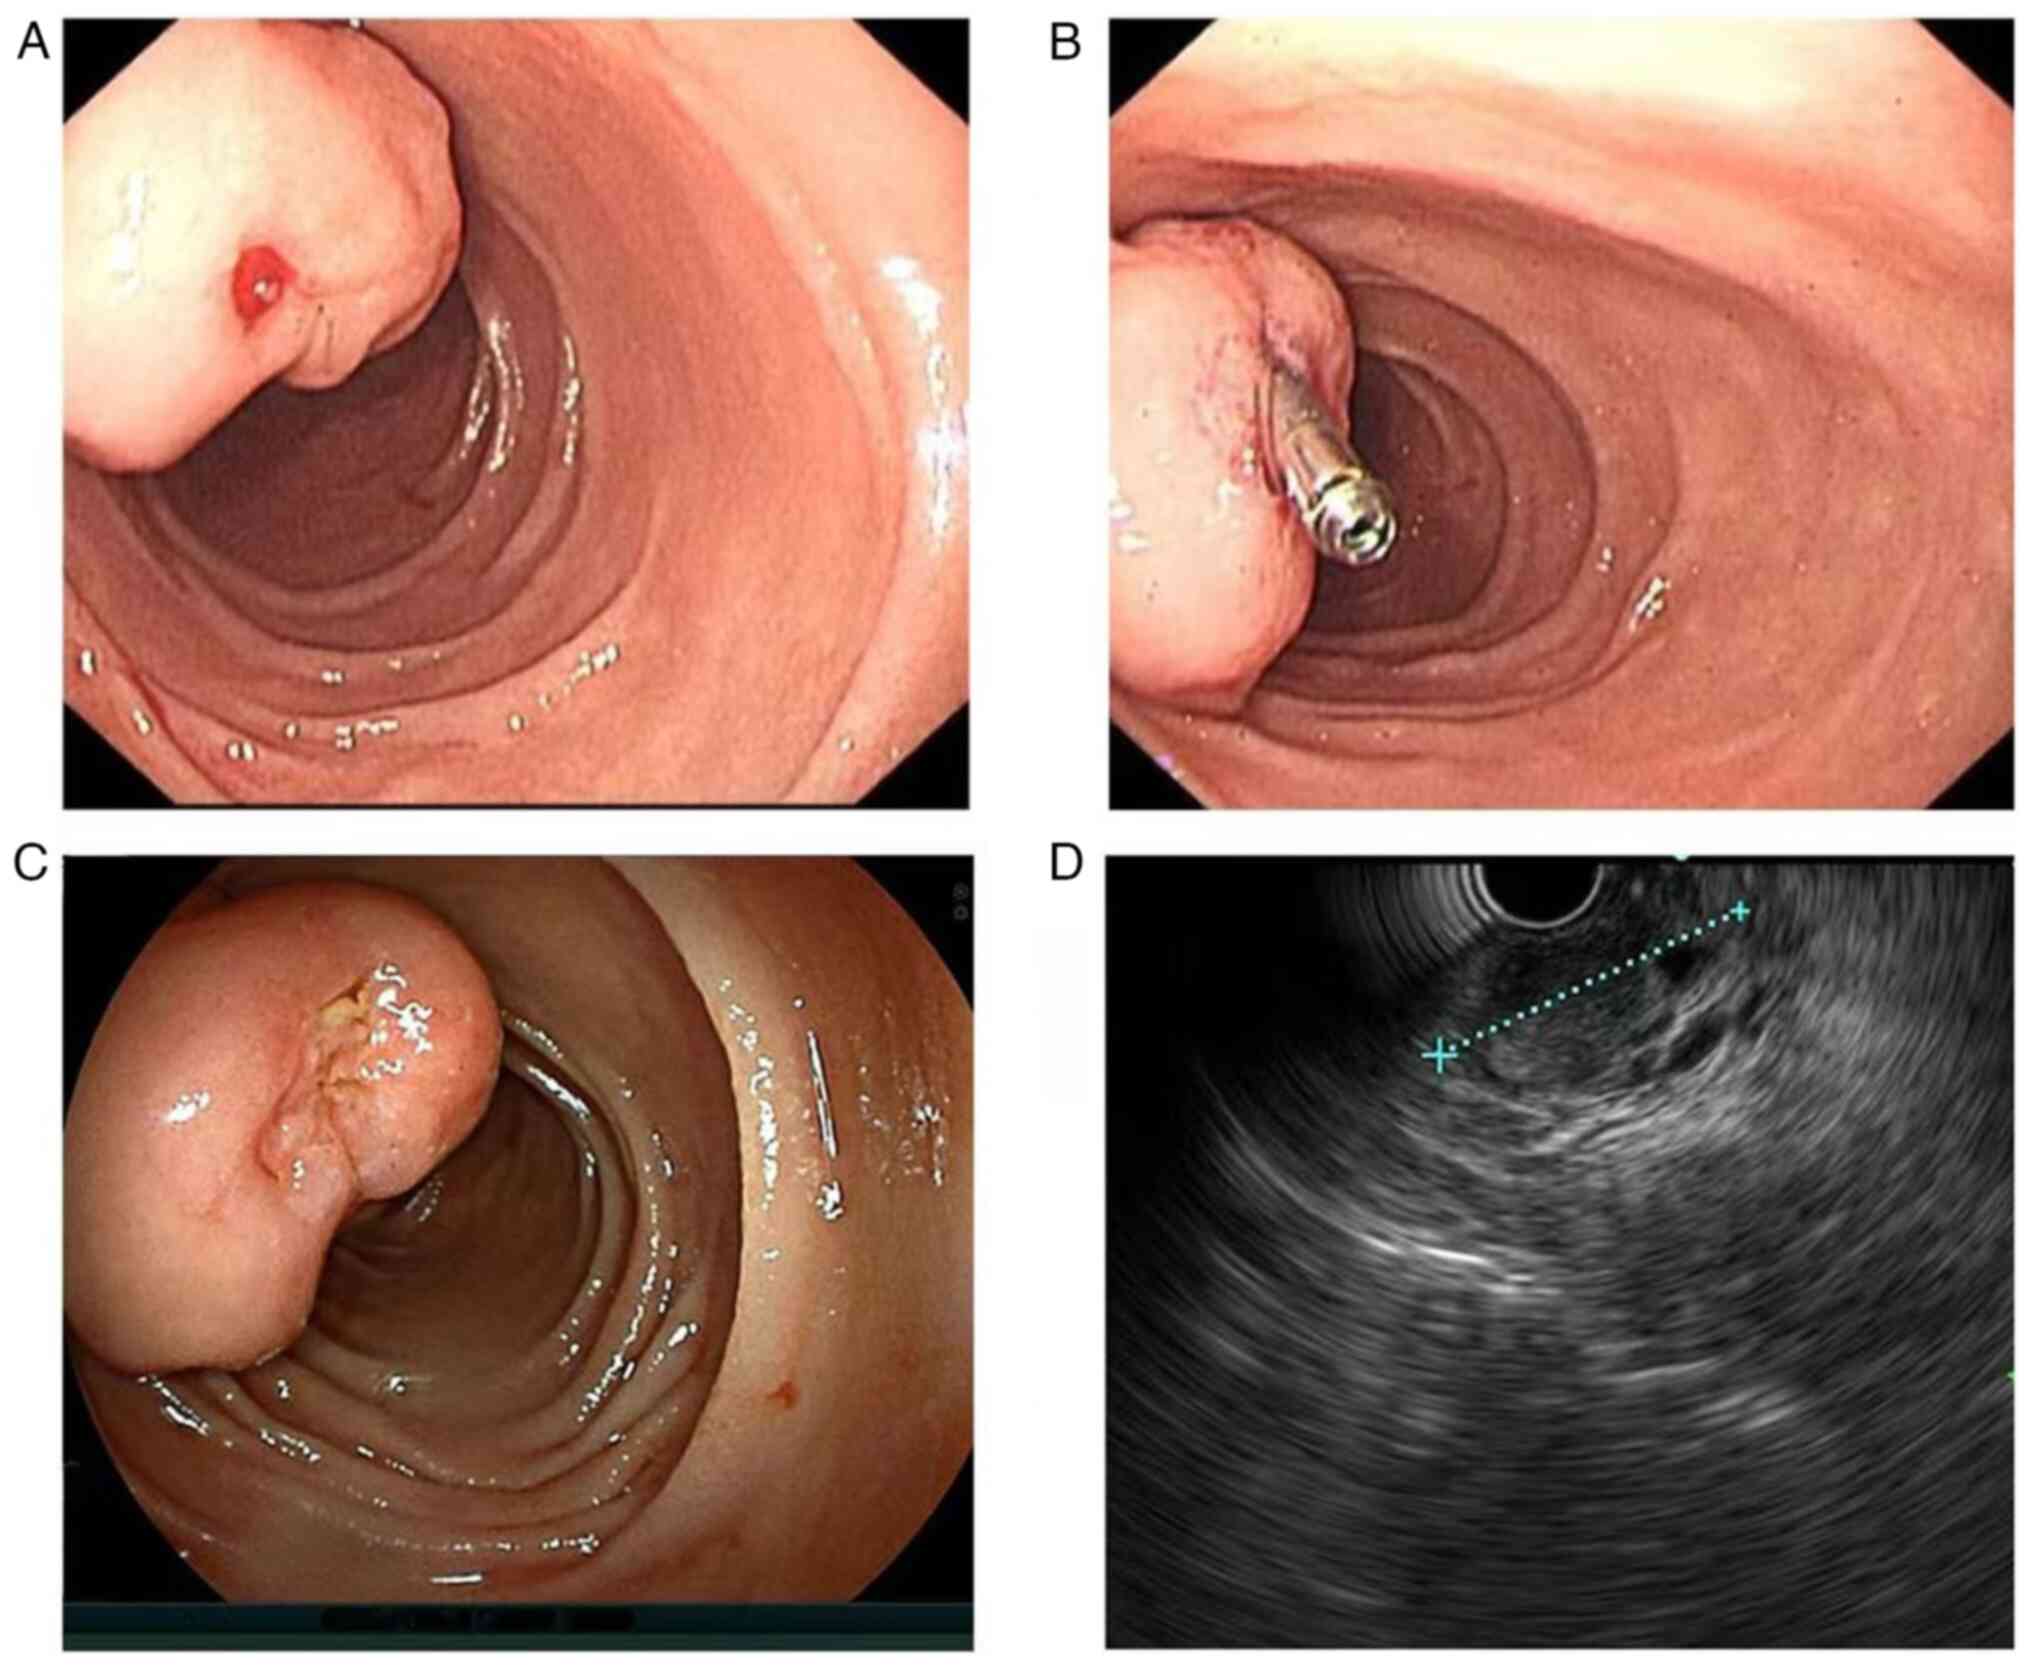

Treatment and management of duodenal gangliocytic paraganglioma: A case report

Gangliocytic paraganglioma (GP) is a rare neuroendocrine tumor primarily found in the duodenum, most commonly in the second and third sections of the duodenum. Diagnosis of GP is based on its distinctive histopathological characteristics, which include three types of tumor cells in varying proportions: i) Epithelioid, ii) spindle‑like and iii) ganglion‑shaped cells. The distribution of the three tumor cell components varies from case to case and a patient may be easily misdiagnosed if one of the components is predominant. Endoscopic submucosal dissection (ESD) or surgical resection is the ideal treatment for duodenal GP (DGP); however, biotherapy, nuclide therapy, chemotherapy, targeted therapy and immunotherapy can be selected individually for patients with postoperative recurrence, metastasis or not suitable for surgery. In the present study, a male patient with DGP experienced recurrence after ESD surgery, and so received octreotide (Novartis; 30 mg/28 days) for 12 consecutive cycles. The patient had no further symptoms of gastrointestinal bleeding and no new lesions or metastases were observed after 47 months of follow‑up.

Figure 2